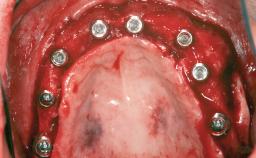

Guided Bone Regeneration (GBR) with a Particulated Autologous Graft and a ePTFE-Reinforced Membrane for Vertical Augmentation of a Single-Tooth Edentulous Space in the Esthetic Zone

# of Implants 1

Type of Implants Two-Piece

Bone Augmentation Staged|Vertical

Augmentation Materials Autogenous chips|Membrane